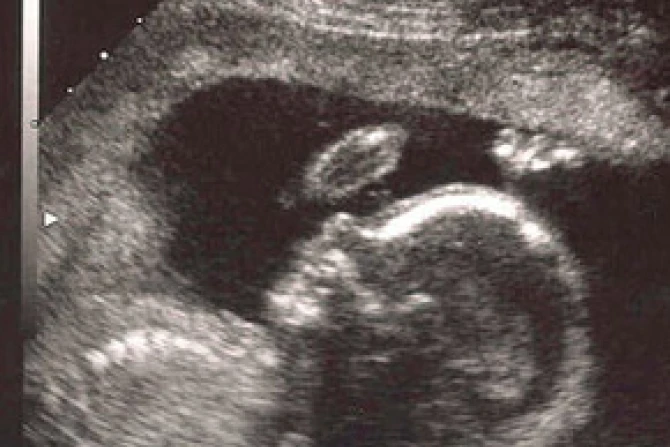

An art design student in Britain has developed a new method to use ultrasound and MRI scans to create life-sized plaster models of living embryos. One leading obstetrician has called the invention “absolutely unique” and a “fantastic development.”

Jorge Lopes, the Brazilian design student whose invention was part of his Royal College of Art doctorate work, calls the method rapid prototyping, the Daily Mail says. The device used is comparable to a printer that prints plastic powder instead of ink, slowly building a three-dimensional model.